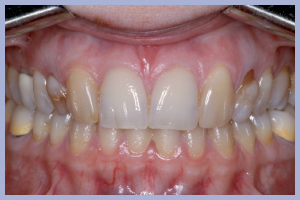

Nel presente caso clinico si tratta della sostituzione implanto-protesica di due incisivi laterali superiori agenesici in una Paziente di sesso femminile. L’agenesia degli incisivi laterali era associata a mesio-dislocazione dei canini al posto degli incisivi laterali e dunque l’obiettivo terapeutico era rappresentato dalla sostituzione dei denti mancanti in zona canina e dalla trasformazione protesica dei canini permanenti presenti in incisivi laterali.

L’esame clinico iniziale (Figg. 1, 2) metteva in evidenza una buona situazione dento-parodontale generale; l’igiene orale e la collaborazione da parte della paziente, fortemente motivata alla soluzione del problema, erano ottime. L’esame radiologico ortopanoramico iniziale (Fig. 3) mostrava una buona quantità di osso apicalmente alle radici degli elementi decidui che apparivano sottili e parzialmente riassorbite. Il progetto terapeutico prevedeva un posizionamento implantare post-estrattivo immediato associato a carico immediato non funzionale tramite l’utilizzo di monconi temporanei e corone in resina precedentemente allestite, da ribasare in bocca dopo la preparazione dei monconi.

- Fig. 1 – Agenesia dei laterali superiori con mesio-dislocazione dei canini permanenti al posto degli incisivi laterali. Visione frontale

- Figg. 2a, b – Visioni laterali dei canini decidui